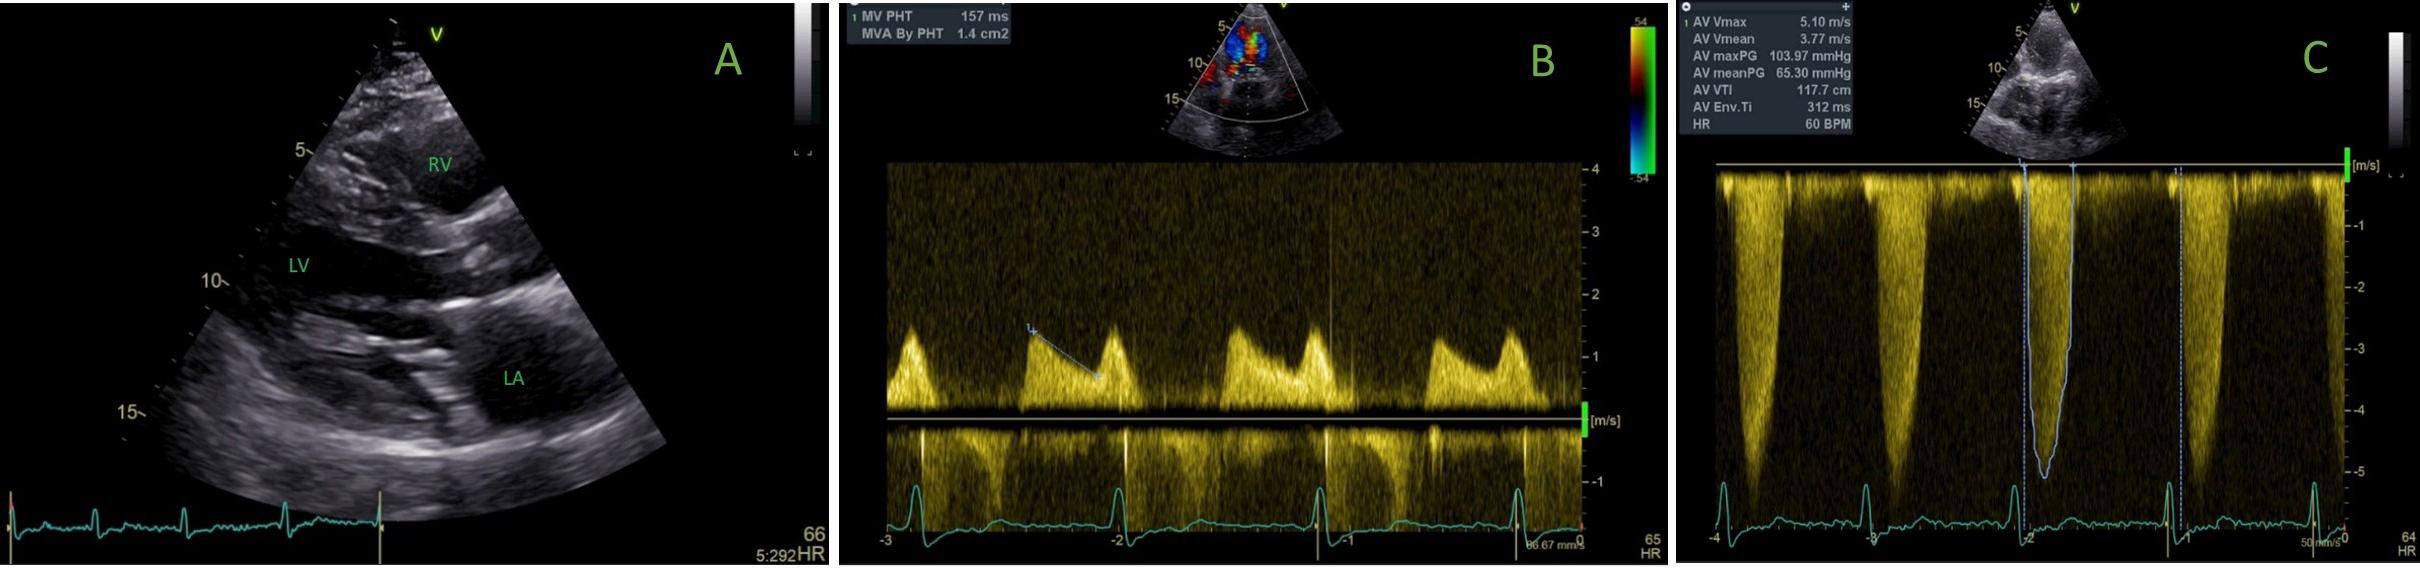

Transthoracic echocardiography in (A) parasternal long axis view showing severe mitral annular calcification and thickened mitral leaflet; (B) four-chamber view demonstrating moderate mitral valve stenosis by the pressure half-time method; and (C) five-chamber view showing severe aortic stenosis by continuous wave Doppler interrogation.

LA - left atrium; LV - left ventricle; RV - right ventricle

Transthoracic echocardiography in (A) parasternal long axis view showing severe mitral annular calcification and thickened mitral leaflet; (B) four-chamber view demonstrating moderate mitral valve stenosis by the pressure half-time method; and (C) five-chamber view showing severe aortic stenosis by continuous wave Doppler interrogation. LA - left atrium; LV - left ventricle; RV - right ventricle